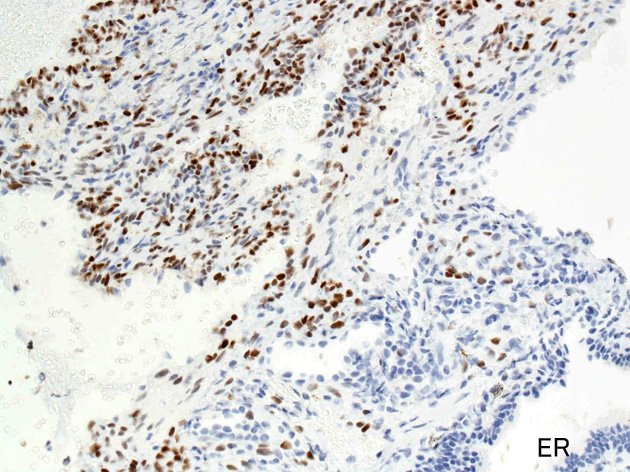

免疫染色

嚢胞周囲または肺血管, リンパ管, 細気管支にそうLAM cellの浸潤, 集簇を特徴とする。LAM cellには2種類が認められ, 小型紡錘形細胞と細胞質の豊富な類上皮様細胞があり, 紡錘型は主に集簇巣の中心に存在し増殖能が高い。 類上皮様LAM cellは辺縁部に多く, 増殖能は低いがHMB45を強く発現している。

LAM cellの免疫染色--SMA, desmin, vimentin(vimentinはいつも陽性とはならない)が陽性となりmuscle lineageであるが典型的な筋細胞と異なり,